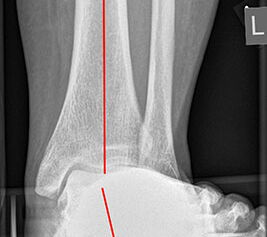

Röntgenaufnahmen des Fußes d.p., streng seitlich und schräg unter Belastung. Saltzmann Aufnahme zur Beurteilung der Rückfussachse.

Operationsplanung anhand der Röntgenaufnahmen unter Beachtung wichtiger radiologischer Landmarks wie Rückfussachse, Metatarsale I – Talushals-Achse im dp und lateralen Strahlengang (Abbildung 1 und 2).

Abbildung 2